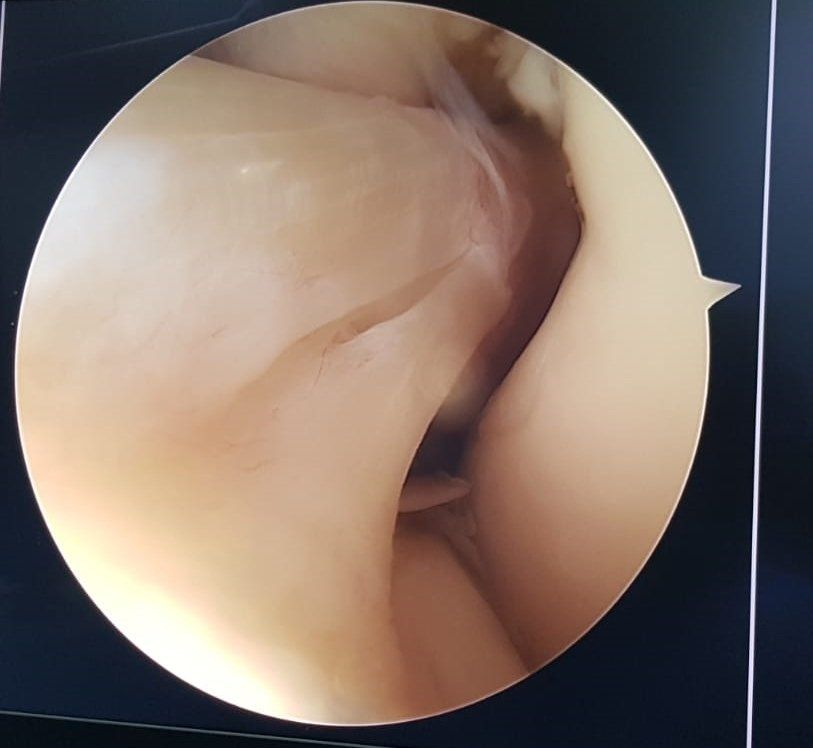

Lesioni osteoarticolari

Le lesioni osteoarticolari derivano da traumi quali lussazioni, fratture, distorsioni, contusioni o tendiniti che a loro volta causano l'usura delle cartilagini o il deterioramento dei tendini ; le più comuni riguardano il gomito, il polso, l'anca, la spalla, il ginocchio e la caviglia specialmente se il soggetto colpito pratica attività sportiva.